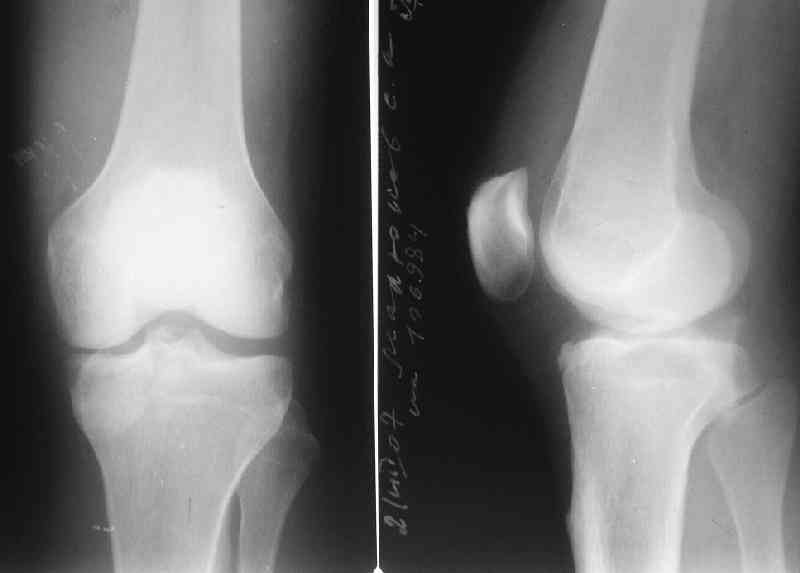

Молодой человек(27 лет) получил травму в ДТП 2 недели назад(23.07).Хотелось бы получить ответы на следующие вопросы:1.Какой доступ предпочесть?

2.Чем фиксировать? Заранее спасибо за конструктивные ответы.